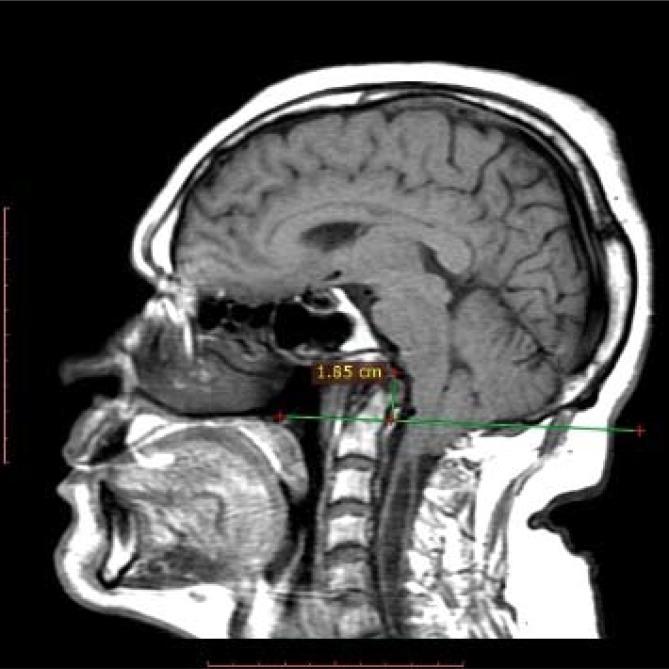

Basilar invagination (BI) and Chiari malformation type I (CM-I) are very important anomalies that introduce instability and compression in the occipitocervical transition region and have complex clinical characteristics. These anomalies vary according to the affected structures. The present study revises current knowledge regarding the anatomy, anatomo-physiology, clinical manifestations, and radiological findings of these entities and the associated surgical treatment approaches. A bibliographic survey was performed through a search in the Medline, PubMed, SciELO, Science and LILACS databases. When associated, these craniovertebral malformations result in neurological deficits due to neural parenchyma compression; however, the presence of microtraumas due to repetitive lesions caused by the bulb and cervical marrow instability has been highlighted as a determinant dysfunction. Surgical treatment is controversial and has many technical variations. Surgery is also challenging due to the complex anatomical characteristics and biomechanics of this region. Nevertheless, advances have been achieved in our understanding of related mechanisms, and compression and atlantoaxial instability are considered key elements when selecting the surgical approach.

颅底凹陷症(BI)和 Chiari 畸形 I 型(CM-I)是非常重要的异常,它们会导致枕颈过渡区不稳定和受压,并具有复杂的临床特征。这些异常根据受影响的结构而有所不同。本研究回顾了这些实体的解剖学、解剖生理学、临床表现和影像学发现以及相关的手术治疗方法的现有知识。通过在 Medline、PubMed、SciELO、Science 和 LILACS 数据库中进行文献检索,进行了文献综述。当这些颅颈畸形合并存在时,由于神经实质受压会导致神经功能缺损;然而,由于球部和颈髓不稳定引起的反复损伤导致微创伤的存在已被确定为功能障碍的决定因素。手术治疗存在争议,并且有许多技术变化。由于该区域的复杂解剖学特征和生物力学特性,手术也具有挑战性。尽管如此,我们对相关机制的理解已经取得了进展,并且在选择手术方法时,认为压迫和寰枢关节不稳定是关键因素。